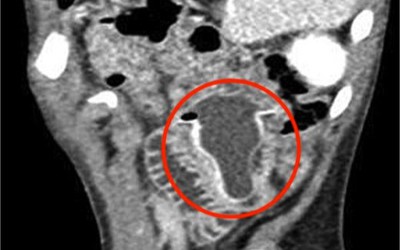

Bé gái 14 tuổi đau bụng, nôn mửa suốt 1 tháng, khi phẫu thuật bác sĩ lấy ra thứ không ngờ

Bé gái 14 tuổi đã phải chịu đựng các cơn đau dạ dày và nôn mửa trong suốt hơn 1 tháng. Kết quả chụp CT cho thấy một "vật thể lạ" khổng lồ chiếm phần lớn khoang dạ dày, kéo dài từ vùng thượng vị tới rốn.